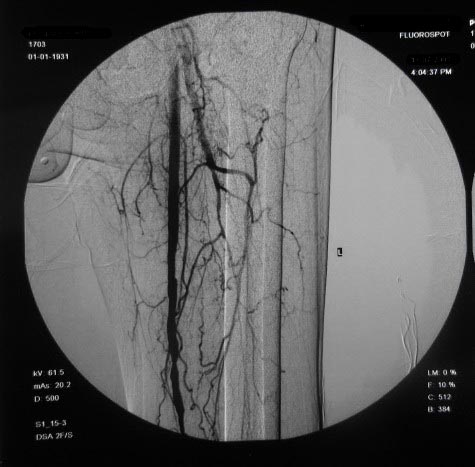

左下肢:

右侧股浅动脉上、中段多处狭窄,下段闭塞。左侧股浅动脉多处狭窄,国动脉起始部狭窄。可以用球囊扩张配合动脉内溶栓或股浅动脉支架置入。多为糖尿病所致。

血管弥漫性病变,可用球囊治疗,但效果不理想

双侧股动脉及腘动脉多发狭窄,右股动脉下段闭塞并侧支形成。病变较广泛,球囊可试试,如病人经济不好,最好还是以药物治疗为主。个人意见。